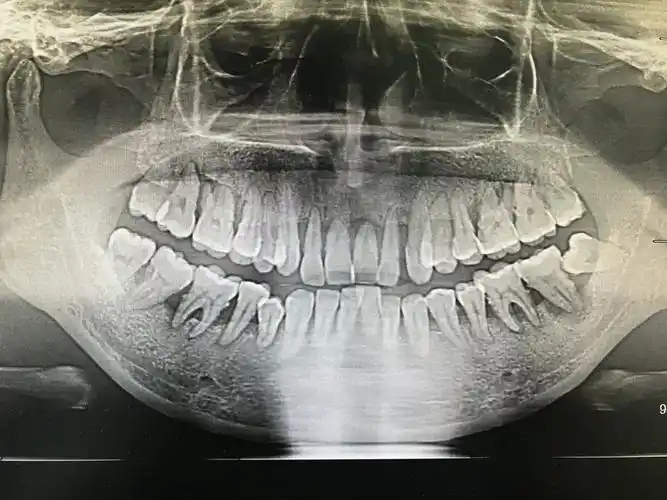

孕期重度牙周病